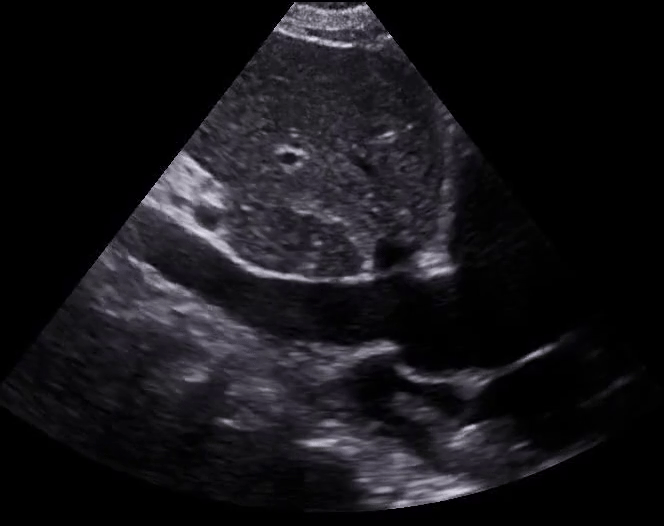

Clip 2: Parasternal Short Axis: increased RV pressures are pushing the interventricular septum towards the left side of the heart creating a ‘D-sign’ shape of the LV.